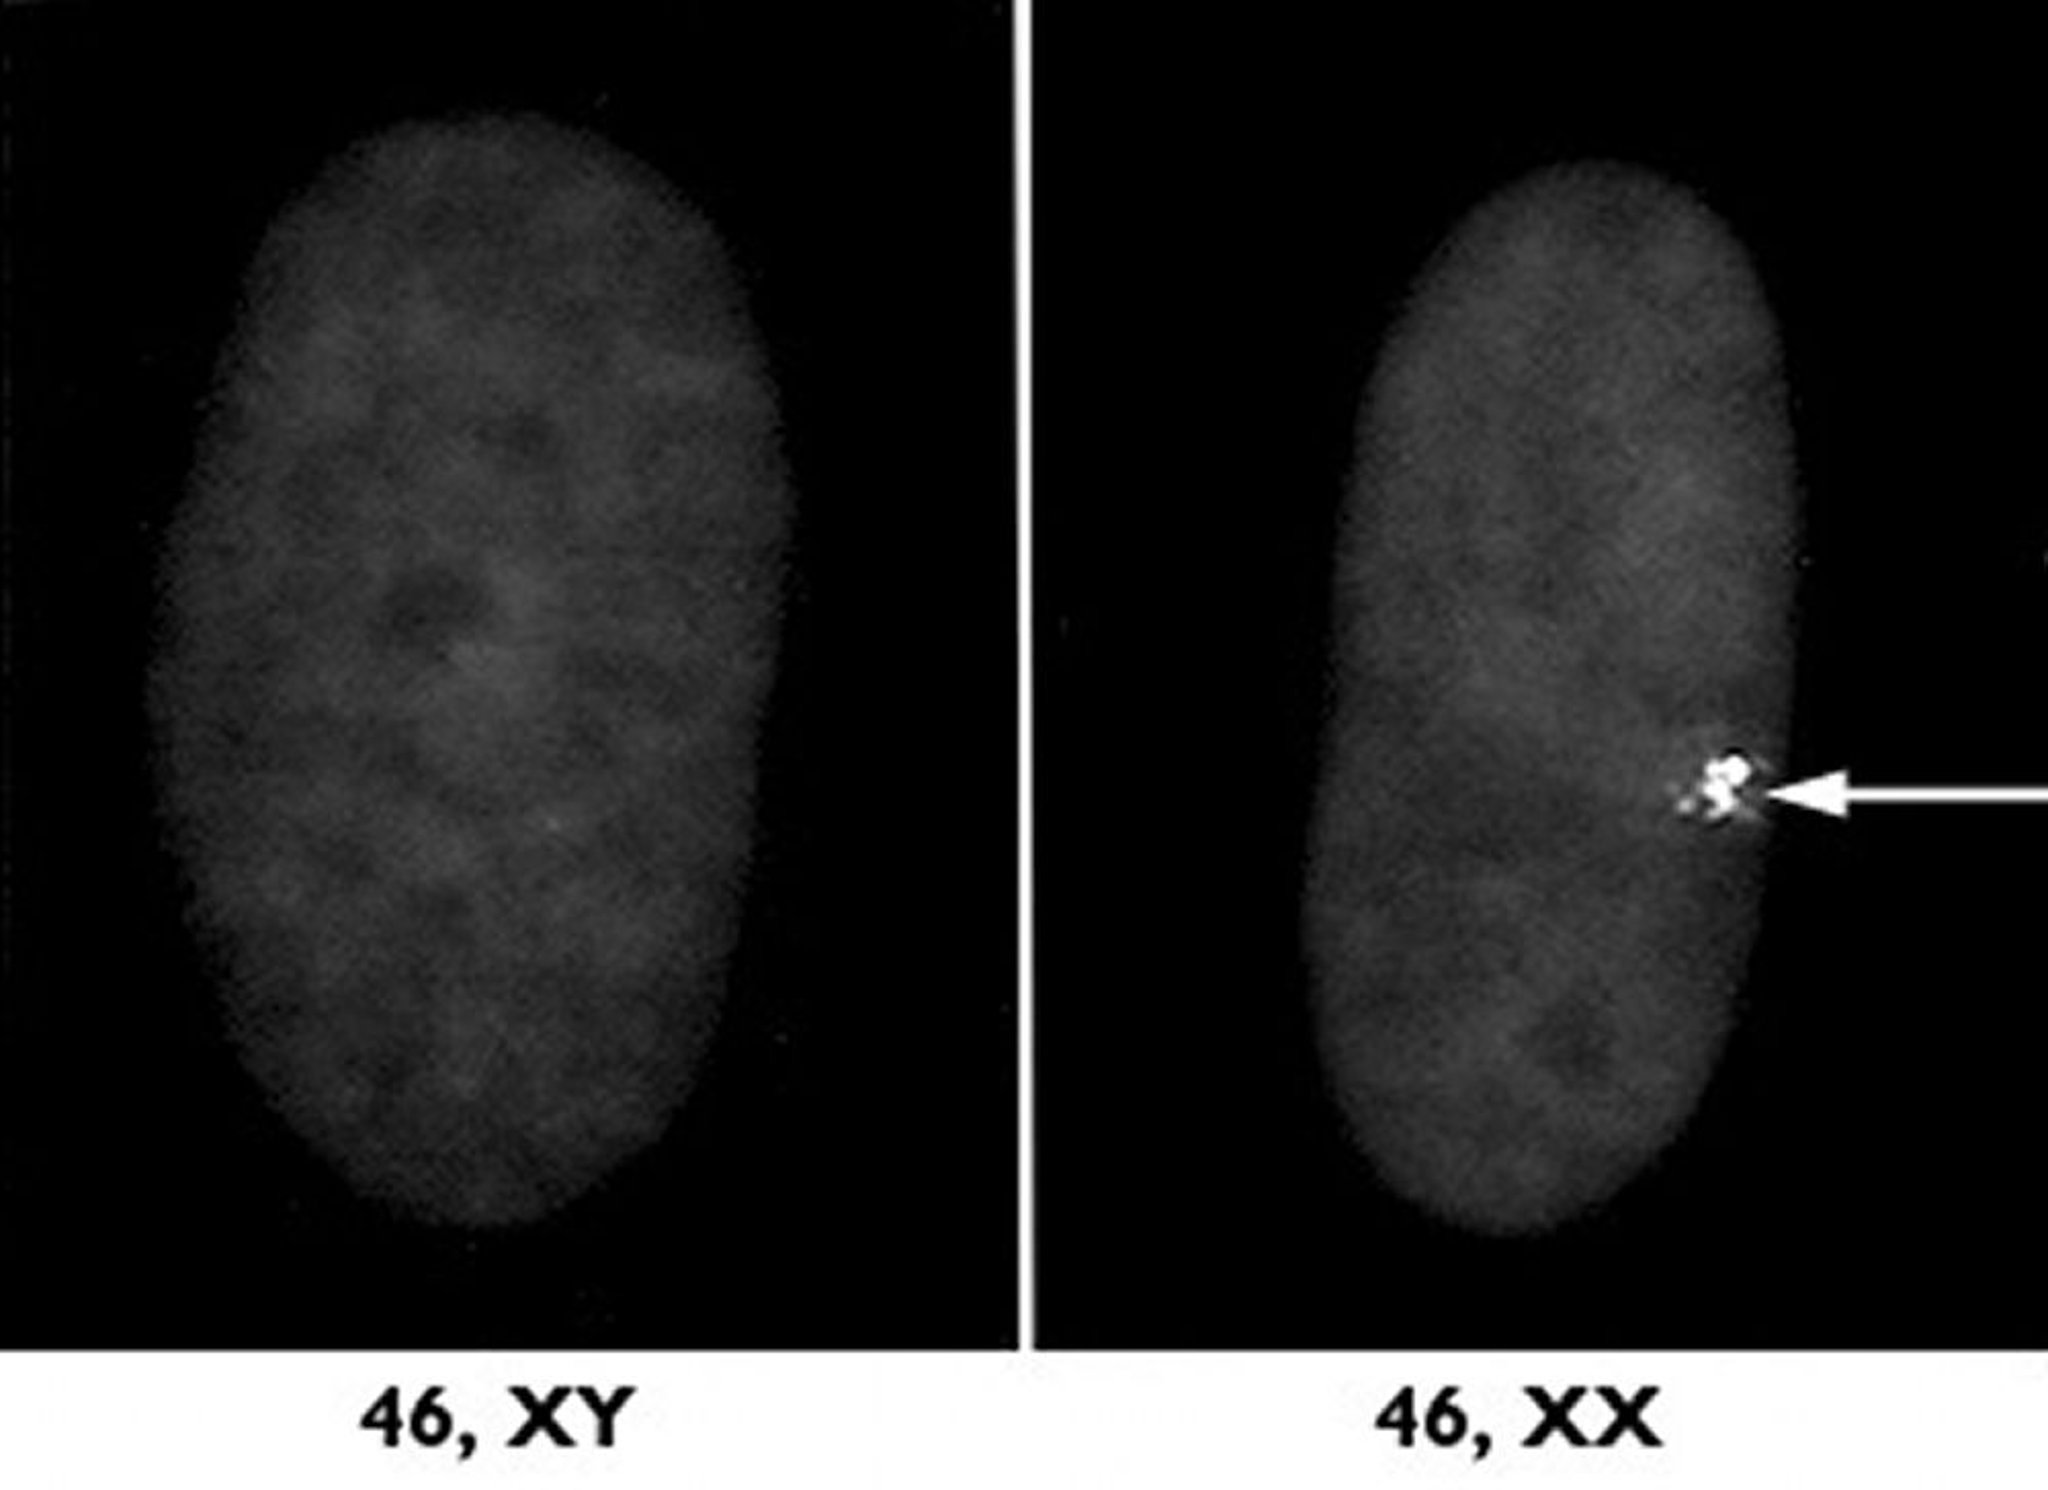

Cromossomo X inativo

Um dos dois cromossomos X femininos é desativado durante um processo chamado inativação do X. À direita, uma amostra microscópica de um núcleo celular feminino mostra esse cromossomo X inativo, como um aglomerado denso (seta). À esquerda, uma amostra masculina é mostrada para comparação.

Cortesia do Dr. L. Carrell e do Dr. H. Williard, Case Western Reserve University School of Medicine.